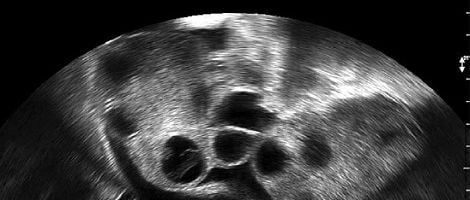

A monitorização é feita através de ecografias periódicas. A sua finalidade é controlar o número de folículos em cada um dos ovários, programar o momento da inseminação e medir a grossura do endométrio.

O ginecologista observa o processo de amadurecimento dos folículos. Quando estes alcançam o tamanho adequado (18 mm de diâmetro) são considerados maduros e a hormona hCG é administrada com o objectivo de desencadear a ovulação.